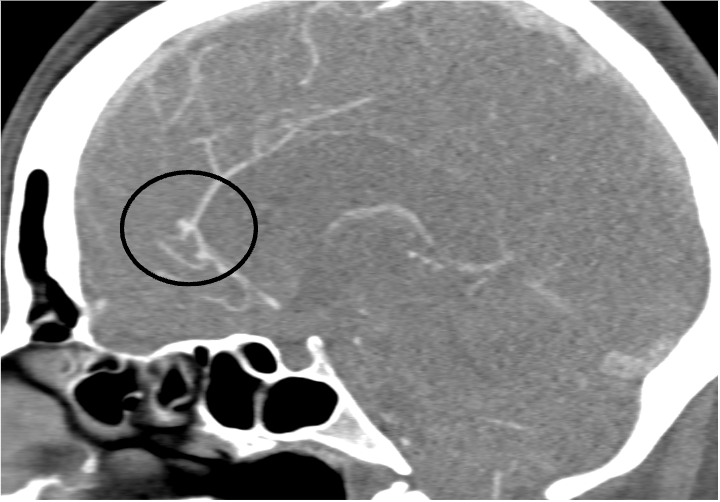

Angio-TC craneal (reconstrucción sagital LADO IZQUIERDO).